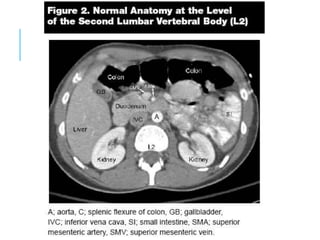

CT SCAN